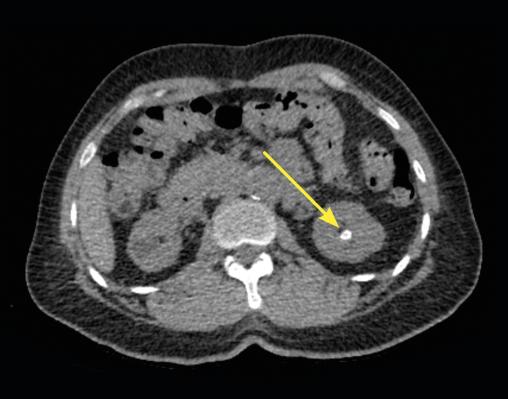

En raison de la taille du calcul, qui expose à un risque de migration symptomatique urétérale, l’ablation urétéroscopique est décidée et réalisée de manière élective une fois le traitement anticoagulant de l’embolie pulmonaire terminé. L’intervention se déroule sans complication (lithotripsie au laser in situ et extraction du calcul) [fig. 3]. Le patient est rentré chez lui vingt-quatre heures heures plus tard.